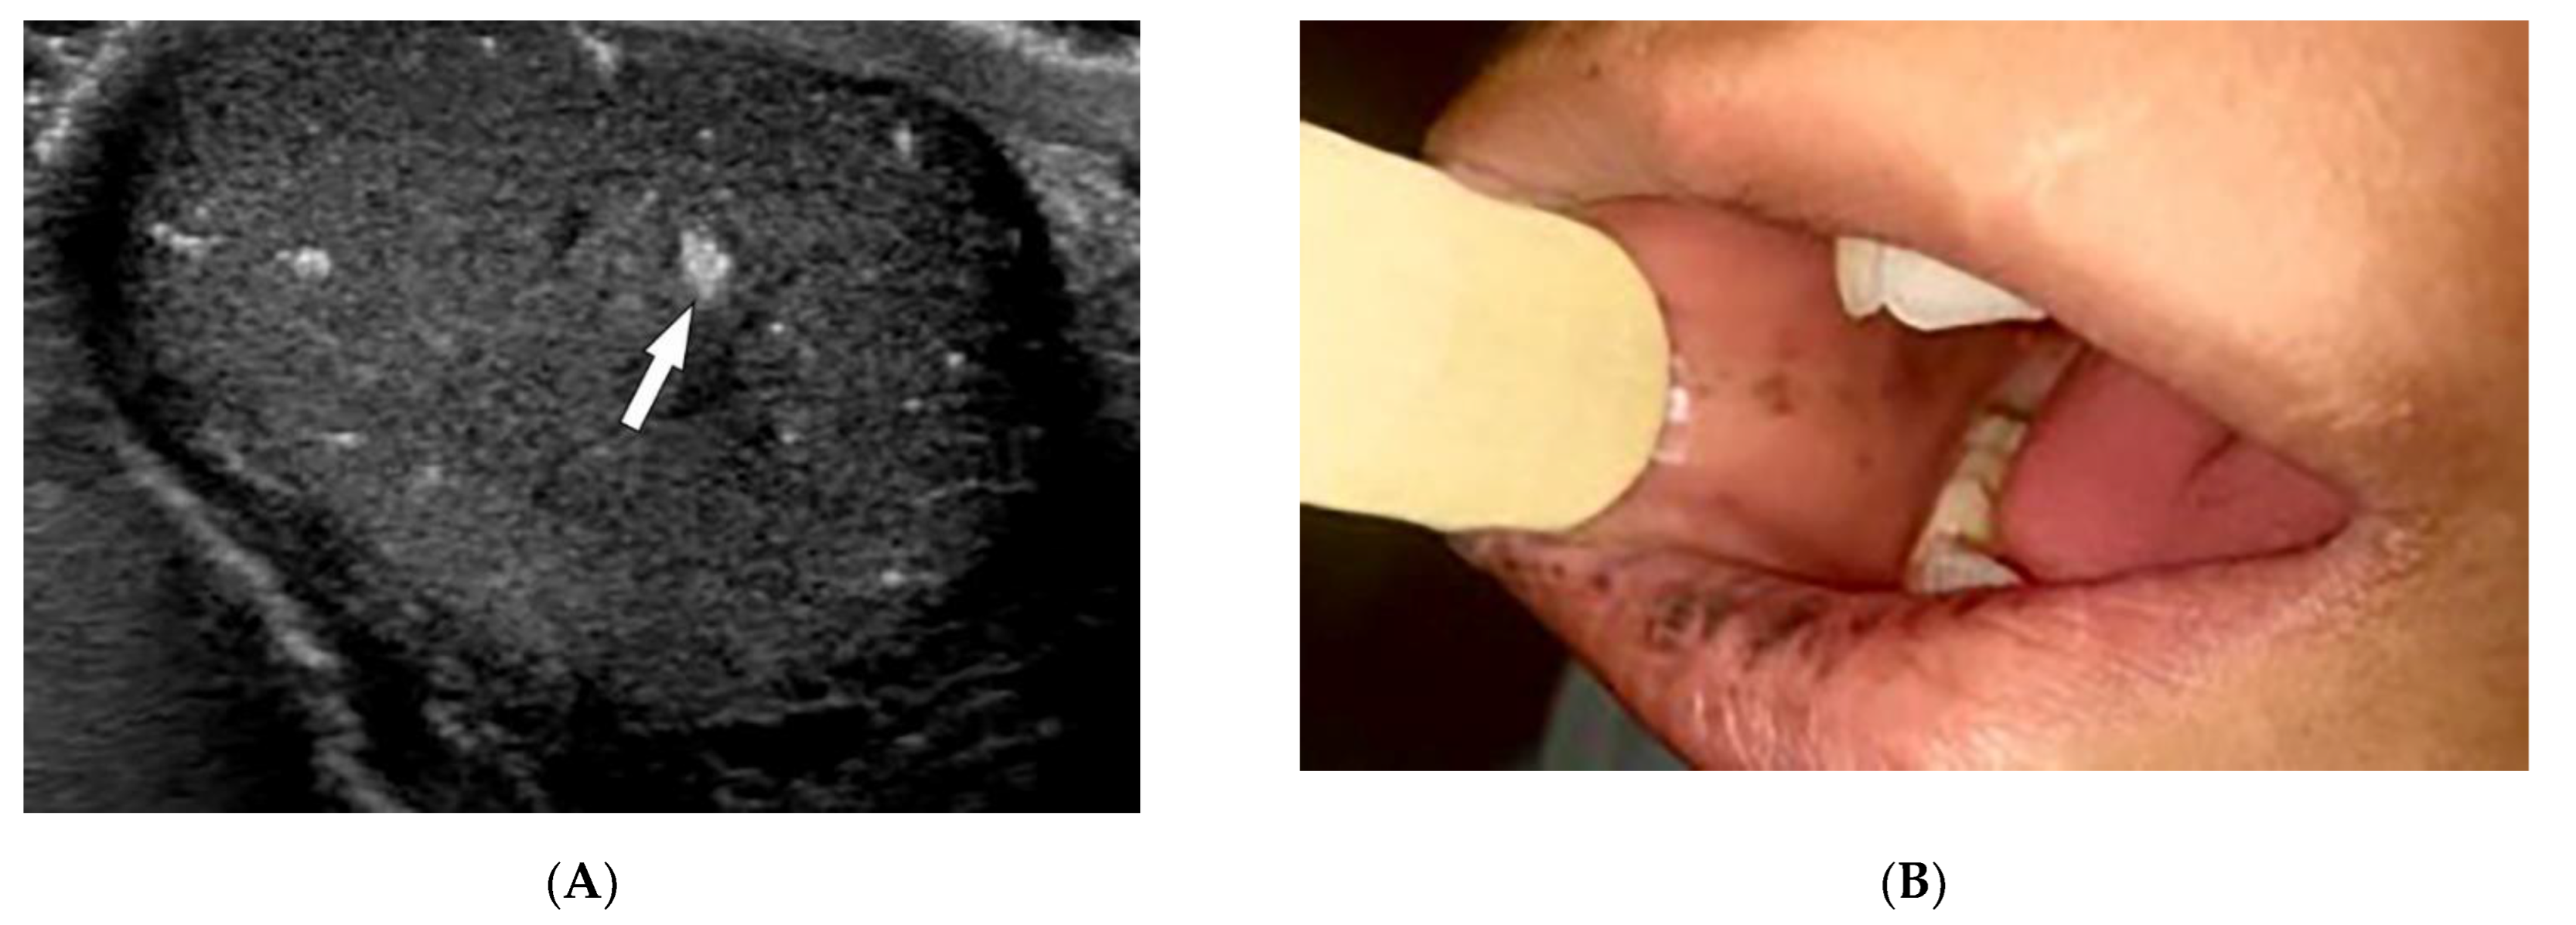

- Dzwigala, M.; Sobolewski, P.; Maslinska, M.; Yurtsever, I.; Szymanska, E.; Walecka, I. High-resolution ultrasound imaging of skin involvement in systemic sclerosis: A systematic review. Rheumatol. Int. 2021, 41, 285–295. [Google Scholar] [CrossRef]

- Hughes, M.; Bruni, C.; Cuomo, G.; Delle Sedie, A.; Gargani, L.; Gutierrez, M.; Lepri, G.; Ruaro, B.; Santiago, T.; Suliman, Y.; et al. The role of ultrasound in systemic sclerosis: On the cutting edge to foster clinical and research advancement. J. Scleroderma Relat. Disord. 2021, 6, 123–132. [Google Scholar] [CrossRef]

| Scleroderma (diffuse systemic sclerosis) | Raynaud’s phenomenon Skin tightening Sclerodactyly Calcinosis cutis Dilated bowel/esophagus Pulmonary hypertension ILD | Soft-tissue calcifications and acro-osteolysis Lack of peristalsis and esophageal dilation NSIP and UIP |